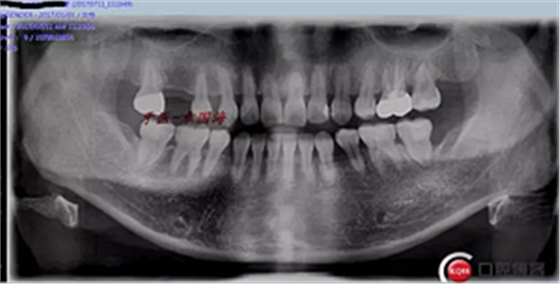

在模型上畫出牙齦高度。(全景片可以大致看出)

附另外一種植前后圖: